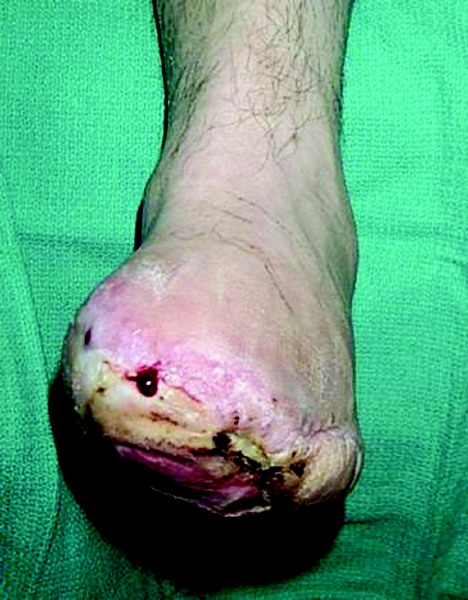

While it is of paramount importance to leave only viable tissue when performing an amputation, it is not always an easy call to make. The decision to leave “marginal” tissue has been the cause of many failed surgeries. Infection, ulcerations, necrosis and fibrotic tissue or dysvascular tissue can all predispose the surgery to fail. A failed amputation can mean the need for revision and exposing the compromised patient to further risk of anesthesia.2 There is an inherent desire on the part of the surgeon, and indeed the patient, to leave as much length as possible during an amputation. However, leaving even any question of potentially infected tissue within the wound is inadvisable and foolhardy. That said, identifying affected tissue can be difficult in cases that are marginal.5-7 There are some important signs to consider when evaluating patients. Strep infections, which are most destructive to tissue of all origins, cause hemorrhagic changes that are clearly visible as dark red, maroon and/or black color changes to connective tissues, blood vessels and muscle tissue. Staph infections may be more commonly represented by purulence. While the adjacent tissue may not have become compromised, it is necessary in this case to perform an atraumatic exploration of all potential spaces for further presence of infection. This is a learned skill that requires considerable caution and care. By exploring adjacent spaces, the surgeon may inadvertently spread infection. It is important to not only have an ingress into a compartment, but also to have an egress to allow for drainage of potentially infected materials.8-10 It is imperative to visualize all tissue that may have been contiguous with known areas of infection. Under pressure, infectious fluids will extrude from one compartment to the next along anatomic lines.11, 12 Van Baal states in Clinics of Infectious Disease that “Proper debridement and drainage of the infection requires a sound knowledge of foot anatomy. The usual routes of progression of the infection along anatomic pathways must be understood.”13 Reviewing the compartments of the foot will aid both novice and experienced surgeons in ensuring a knowledgeable exploration of potential areas of infection progression.

Failure to appropriately assess healing potential from a vascular standpoint may be the single most critical error made in pre-planning for amputation level. If the surgeon considers the surgery as an “inciting event” for the patient, it is easier to view it as an event that will require increased metabolic demand to heal. Methods for assessing the patient’s ability to heal from a vascular standpoint include the ankle-brachial index (ABI), the toe-brachial index (TBI), transcutaneous oxygen pressure monitoring (TCPO2) and angiograms. The ABI (the ratio of the systolic pressure in the ankle to that in the arm) is known to be a poor predictor of healing when it is at a level of greater than 1.1, indicating calcification of the vessels in the diabetic. Perfusion is better indicated by the TBI (the ratio of the systolic pressure in the hallux to that in the arm).16, 17 In the works by Bacharach, Rooke and Osmundson, a TCPO2 greater than or equal to 40 was associated with primary or delayed healing in 98 percent of limbs undergoing amputation while a TCPO2 value of less than 20 was “universally associated with failure.”18 Angiograms remain the central tool for intervention if one anticipates the need for vascular reconstruction. Modern techniques that target smaller vessels in patients with lower limb vascular disease require very precise imaging of the peripheral vessels preoperatively.19 Several studies have shown that a positive outcome of these distal bypass procedures is governed by exacting determination of adequate pedal perfusion, requiring preoperative identification of the vessels.20,21 Failure to do so can result in further, unnecessary amputations. One may successfully limit surgery to an anatomic area with fair circulation while the rest of the foot is compromised. For example, no palpable posterior tibial pulse would predispose a plantar flap to failure but a strong dorsalis pedis might allow for healing of a distal toe amputation. In the case of the scheduled amputation, one must assess vascular disease (both focal microvascular and macrovascular) prior to the surgery. For the emergency case, the infection requires attention before the need for vascular assessment. In this setting, a revisional amputation may be required if the vascular test results do not indicate healing potential at the previously chosen level of amputation. It is important to remember that a palpable pedal pulse does not guarantee adequate circulation and perfusion is necessary to heal a surgery. Keep in mind that patients with diabetes commonly have calcified vessels, giving falsely elevated indicators of circulation. When it comes to patients with gangrene and diabetic complications, researchers have suggested amputating at a level with good, documented circulation.22 Another research group had success in assessing healing potential by using the amount of intraoperative bleeding from the skin flap. If it did not bleed sufficiently, they revised the amputation to a higher level.23 This technique is commonly used and highlights one reason for not employing a tourniquet during amputation procedures or at least letting the tourniquet down upon completion and prior to dressing.